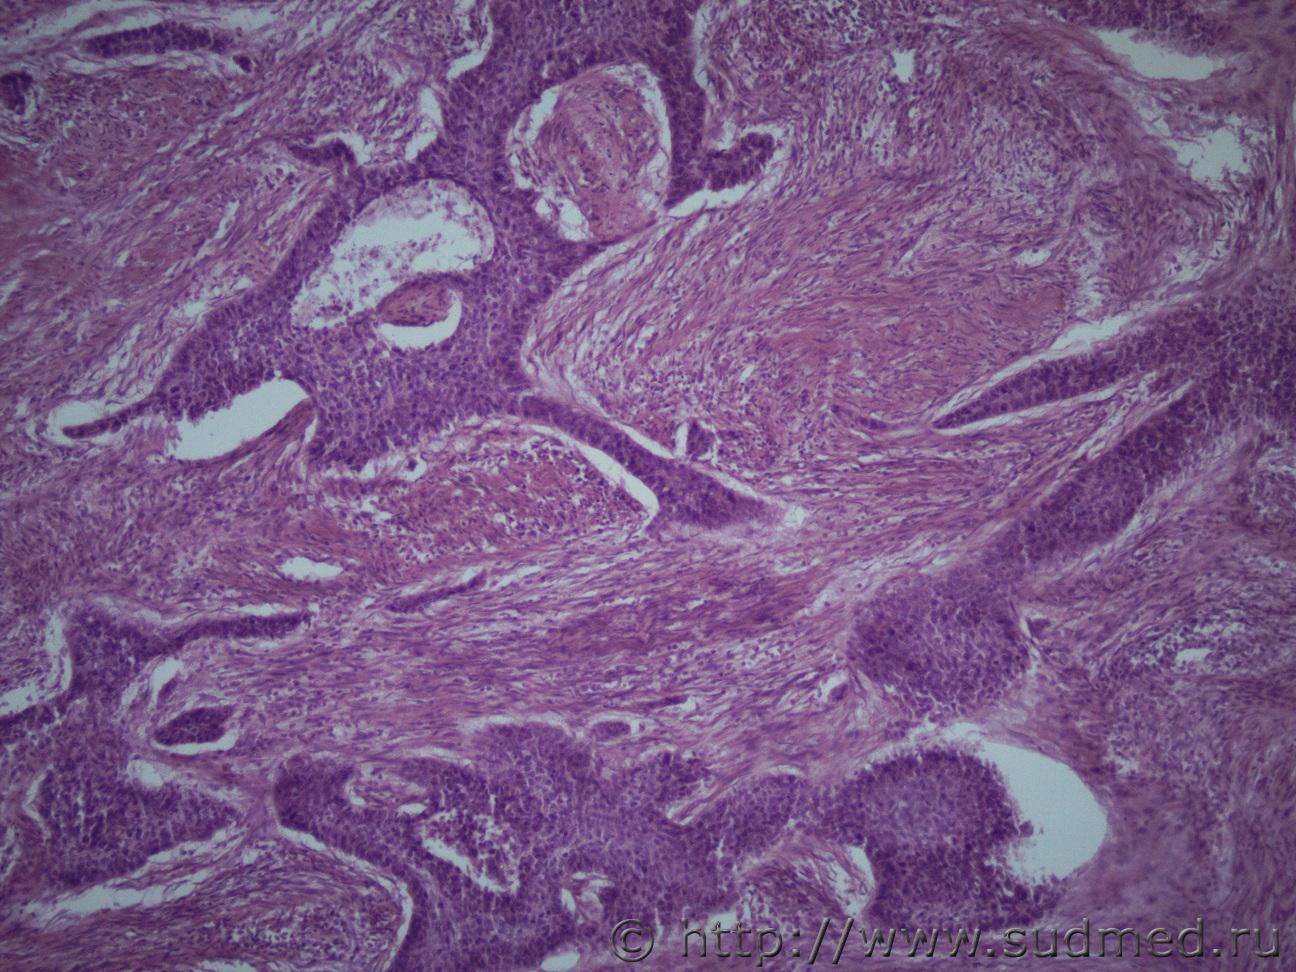

Ув. коллеги, это опять я. Сегодня день опухолей))) Жен 1984 г.р Опухоль матки Судебная медицина - Прикрепленное изображение Судебная медицина - Прикрепленное изображениеСудебная медицина - Прикрепленное изображениеСудебная медицина - Прикрепленное изображениеСудебная медицина - Прикрепленное изображение

Плоскоклеточный низкодифференцированный рак.

Согласен. Имеет место базальноклеточная плоскоклеточная карцинома, возможно метастатическая.